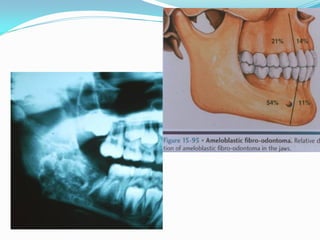

Ameloblastic Fibro-odontoma

 This lesion is defined as a tumor with general features

of an ameloblastic fibroma but containing enamel and

dentin.

 Some investigators believe that this entity is but a

stage in the development of an odontoma ; however,

most agree that progressive destructive tumors are

true neoplasms.

Ameloblastic Fibro-odontoma: Clinical and

Radiographic Features

 Patient Age: Most common in the 5-12 year age

range with a mean of 10 years.

 Gender Predilection: None.

 Location: It is more common in the

premolar/molar regions of both jaws.

 Radiographic Features: Usually appears as a welldefined unilocular or rarely multilocular

radiolucency with variable amounts of calcified

material which is radiopaque. Therefore, it may

appear as a mixed, radiolucent-radiopaque lesion.

Ameloblastic Fibro-odontoma: Treatment

and Prognosis

 The ameloblastic fibro-odontoma is usually

treated by conservative curettage with the

lesion separating easily from the

surrounding bone.

 Prognosis is excellent and recurrence is

unusual.